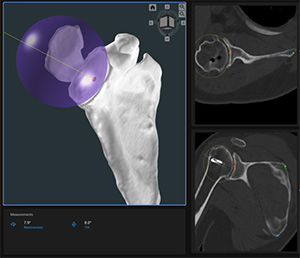

FYI: The Precision AI Planning Software is intended to be used as a pre-surgical planner for simulation of surgical interventions for shoulder joint replacement. The software is used to assist in the positioning of shoulder components by creating a 3D bone construct of the joint that allows the surgeon to visualize, measure, reconstruct, annotate and edit presurgical plan data. The software is used to generate a surgery report and pre-surgical plan data file, which can be used as input data to design the Precision AI Shoulder Guide and Biomodels. The system is indicated for total and reverse shoulder replacement using implant systems from Enovis/Lima.

Precision AI, founded in 2019 by surgeons, mathematicians and engineers, is based in Queensland, Australia.